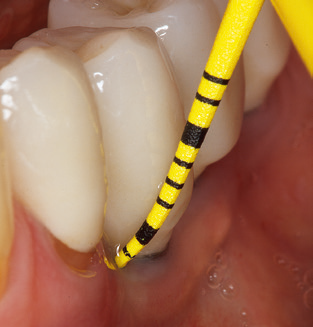

Fig. 4: Flexible probes with millimetre markings are recommended for the probing of dental implants (e.g. Colorvue Kit PCV11KIT6, Hu­Friedy). – Fig. 5a and b: A straight working tip (1P, W&H Dentalwerk Bürmoos GmbH) is a suitable instrument for use on all natural teeth. – Fig. 6: Curved working tips (3Pr/3Pl, W&H Dentalwerk Bürmoos GmbH) lend themselves to the processing of difficult-to-reach areas of the tooth and root surfaces (e.g. furcations). – Fig. 7: The tapered, hexagonal implant cleaning tip (1I, W&H Dentalwerk Bürmoos GmbH) permits atraumatic and efficient cleaning of the crown and abutment surfaces. – Fig. 8: Titanium and carbon curettes are suitable instruments for the manual cleaning of the implant surfaces.

Updating the patient’s medical history is an important aspect of SPT and should occur at least once per year. It helps the dental team to identify and document any new risk factors. Especially when a patient is treated over many years, it is important to establish whether patient-specific and general health risk factors have changed. This primarily concerns a heightened risk as a result of diabetes, but other general conditions (cardiovascular disease and neoplasia) can also produce a modified risk profile as a result of the treatment performed and medication administered. Accordingly, updating the medical history as part of SPT is very important, as a modified risk profile may trigger the need to adapt the treatment interval. In the next step, it is important to afford the diagnostics due attention. Whilst instruments are a central aspect of SPT, findings and their documentation must never be neglected. The periodontological findings are essential for a good diagnosis; increases in the pocket depths and the BOP index are clear indicators of advancing periodontal and peri-implant disease. As such, the team should not shy away from probing implants too, with the aim of gathering the requisite data. At the same time, it is important to use periodontal probes with millimetre markings. Metallic probes have already been used for determining pocket depths around natural teeth for decades. In the case of implants, the challenge of recording correct and reproducible pockets depths is even greater. As the discrepancy between the implant diameter and the contour of the superstructure regularly results in overcontouring of the superstructure, flexible probes which still feature millimetre markings are a sensible solution for measuring pocket depths around implants (e.g., Colorvue Kit PCV11KIT6, Hu­Friedy; Fig. 4).